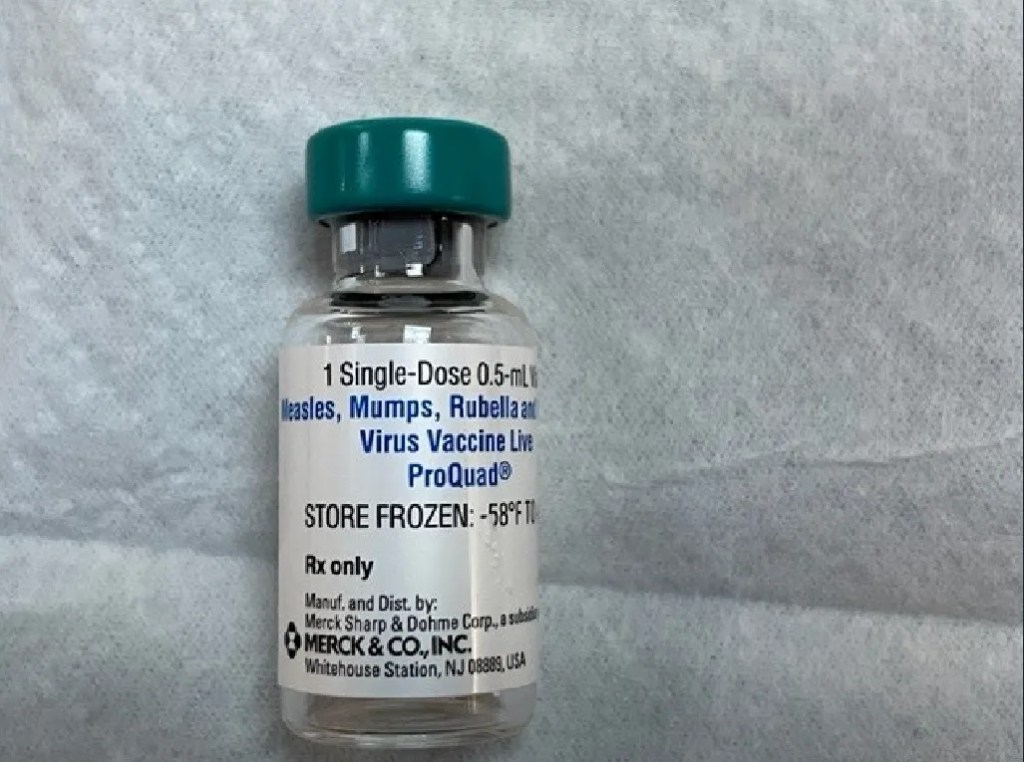

Iată ce a descoperit: Vaccinul MMR din copilărie este încărcat cu nanoboți. Sunt atât de mici încât la cea mai mare mărire a mea abia îi poți vedea, dar sunt clar acolo. Am încercat să merg până la de 4000 de ori cu obiectivul meu Oil, dar nu le-am putut vizualiza. Am făcut multe videoclipuri și dacă te uiți la întreaga documentație, este clar uimitoare. Vax-ul MMRV ar trebui să fie stocat la -56F. Dezghețat, arată exact ca arma biologică C19. Filamentele se asamblează și suprafețe mari de cheaguri de hidrogel. Fără lamelă, autoasamblarea este mult mai vizibilă. Acesta se administrează copiilor de 9 luni, apoi din nou la 15 luni și apoi la 6 ani. Acesta este al 5-lea vaccin din copilărie la care m-am uitat. Totul mi se pare la fel, este încărcat cu nanotehnologie de autoasamblare. Aproape că mă face să mă întreb dacă folosesc aceleași ingrediente, doar pune o etichetă diferită pe ea. Orice medic sau individ care a fost numit vreodată un antivaccinist trebuie să obțină aceste articole (pe care le voi aduna pe toate într-o singură postare, mai am câteva „vaccinuri” de făcut) și să dea în judecată pe oricine i-a acuzat.